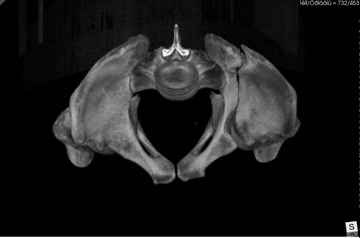

Добрый вечер уважаемые коллеги. Госпитализирован пациент с переломом таза 9-ти месячной давности (лечился где-то в районе консервативно). Помогите определиться с оптимальным вариантом хирургического доступа, фиксации.

Пациенту чуть больше сорока лет, работал в МЧС, после ДТП лечился по месту жительства консервативно. Жалобы пациента на постоянные боли в месте перелома, ощущение подвижности в месте перелома при ходьбе. Передвигается без дополнительной опоры, хромота не щадящая. Клинически отчетливо определяется патологическая подвижность крыла левой подвздошной кости. R-ммы не высылаю, сразу 3-D, если не хватит дошлю снимки.

Андрей, на 3d снимках не видно соотношение суставных поверхностей, величину диастаза в ложном суставе и состояние головки (может уже протез нужен).

Нужны стандартные снимки и срезы на уровне сустава и тела подвздошной кости.